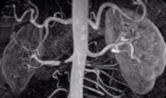

HA secundária de causa renovascular: sinais e sintomas + como diagnosticar e padrão ouro?

A

• Sopro abdominal

• Edema agudo pulmonar de repetição

• Piora renal em IECA/BRA

Diagnóstico:

* Doppler de artérias renais

* Angio TC/RM

* Arteriografia renal (padrão ouro)